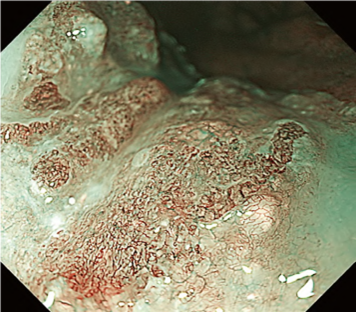

Predicting invasion depth of superficial esophageal squamous cell carcinoma is crucial in determining the precise indication for endoscopic resection (ER) because the rate of lymph node metastasis increases in proportion to the invasion depth of the carcinoma. Previous studies have shown a close relationship between microvascular patterns observed by magnifying endoscopy and invasion depth of the superficial carcinoma. Although there were two major classifications, Inoue and Arima, the Japan Esophageal Society (JES) integrated the two classifications and simplified it and developed a new magnifying endoscopic classification for the characterization and predicting invasion depth of superficial esophageal squamous cell carcinomas (SESCCs). This is essential for developing a treatment strategy for SESCC, in particular the indication for ER. Therefore, in this classification, morphological types of microvessels are classified into two categories of noncancerous [type A: normal epithelium, inflammation, and squamous intraepithelial neoplasia (SIN)] and cancerous (Type B: SCC) lesions. The cancerous types of microvessels corresponding to SESCCs are subclassified into three groups based upon an indication for ER as follows: an absolute indication type (Type B1: T1a-EP or T1a-LPM), a relative indication type [Type B2: T1a-MM or T1b-SM1(tumor invades the submucosa to a depth of 200 μm or less from the muscularis mucosa)], and a contraindication type [Type B3: T1b-SM2 (tumor invades the submucosa to a depth more than 200 μm)]. Diagnostic criteria of the JES classification are based on the degree of microvascular irregularity in the target lesion observed by magnifying endoscopy. Intrapapillary capillary loops (IPCL) are a basic unit of microvasculature in the stratified squamous epithelial layer. The microvascular irregularity is evaluated for the presence or absence of each of the following morphological factors: weaving (i.e., tortuosity), dilatation, irregular caliber, and different shape (i.e., various shapes). Microvessels are classified as type A if they have three or fewer factors (i.e., without severe abnormality; . Fig. 1a) and type B if they have all four (i.e., with severe abnormality). Type B is then subclassified into B1, B2, and B3 (. Fig. 1b–d, respectively) based on the running pattern or degree of dilatation of severely irregular microvessels. The definitions and schemas of type A and B vessels and predicted histology of invasion depth by type B vessels are summarized in . Table 1. A large scale validation study showed high overall accuracy (90.5%) of type B vessels of the JES classification. The most important auxiliary criterion in the JES classification is avascular area (AVA). AVA is defined as a low or no vascularity area surrounded by all subtypes of type B microvessels including B1 vessels. Diameters of AVA are positively correlated with sizes of histological cancer nest and the histological invasion depth of SESCC. Small (<0.5 mm), middle (0.5 ≤< 3 mm), and large (≤3 mm) AVA are suggestive of T1a-EP/ LPM, T1a-MM/T1b-SM1, and T1b-SM2, respectively. A key point to note is that any types of AVA (small, middle, and large) surrounded by B1 vessels are suggestive of T1a-EP or T1a-LPM SCC.